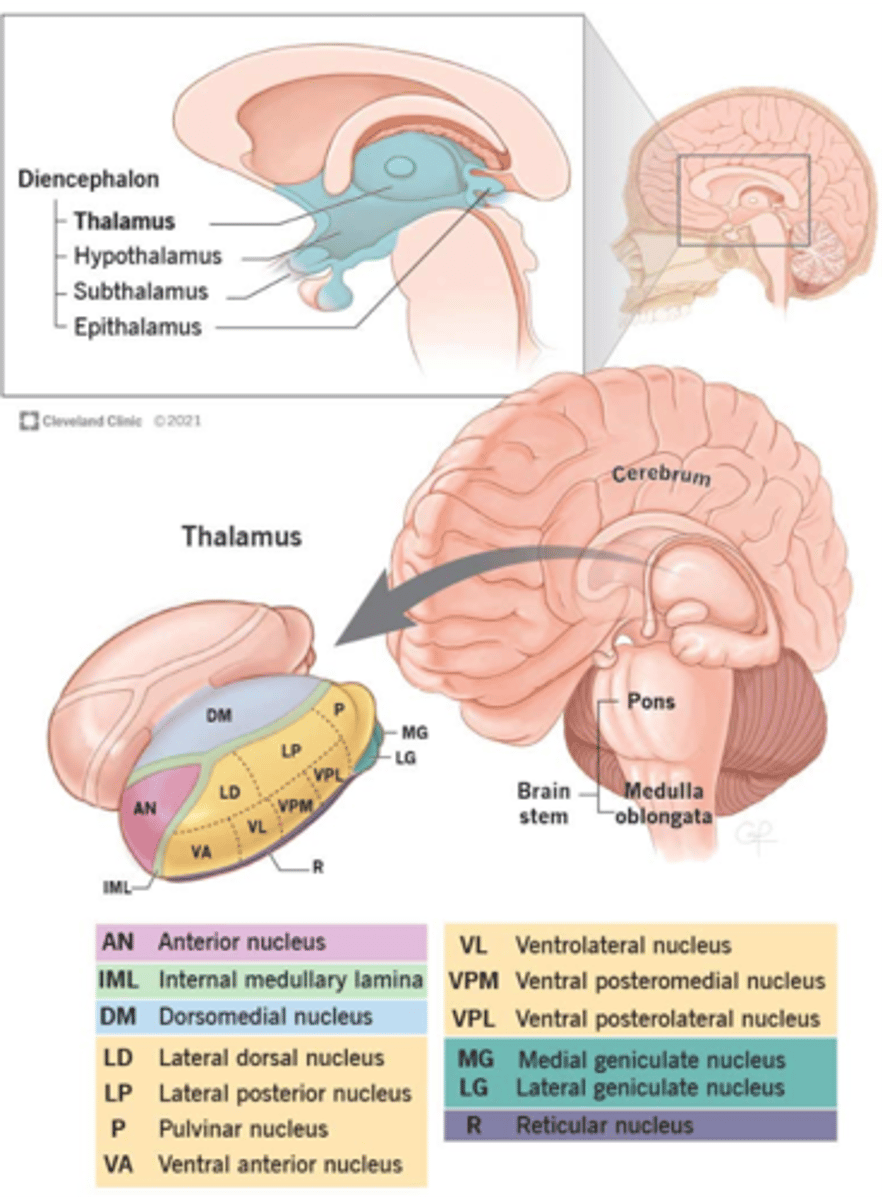

what are 2 important structures of the diencephalon?

1. thalamus

2. hypothalamus

what structure of the diencephalon regulates the of flow sensory and motor information from various location that will ultimately reach the cortex?

thalamus

what structure of the diencephalon is the relay station for all but one sensory tracts on their way to the cortex? what is the exception?

thalamus

olfactory is the only tract to bypass the thalamus and go directly to the cortex

what are 2 key thalamic nuclei?

1. ventral posterolateral nucleus (VPL)

2. ventral posteromedial nucleus (VPM)

what structure of the diencephalon is the main visceral control center of the brain?

hypothalamus

what structure of the diencephalon mediates a wide range of functions through connections with endocrine, autonomic, somatic motor, limbic systems, and maintaining a state of homeostasis?

hypothalamus